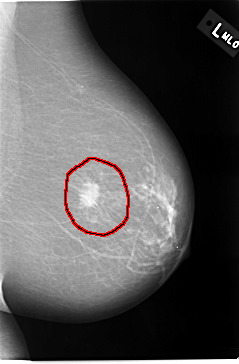

C_0037_1.LEFT_CC

FILE: C_0037_1.LEFT_CC.OVERLAY

TOTAL_ABNORMALITIES 1

ABNORMALITY 1

LESION_TYPE MASS SHAPE IRREGULAR MARGINS ILL_DEFINED

ASSESSMENT 5

SUBTLETY 5

PATHOLOGY MALIGNANT

TOTAL_OUTLINES 1

BOUNDARY